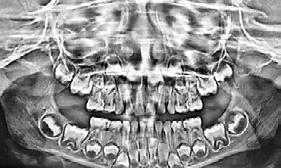

Entre los elementos que conforman al sistema estomatognático, están los dientes caninos, órganos dentales esenciales en la fisiología masticatoria; punto de unión y continuidad estética entre la línea de la sonrisa y el corredor posterior del arco dental, además de que ejercen la función de pilares estabilizadores en la oclusión fisiológica (Figura 1).

Los caninos son indispensables durante los movimientos de lateralidad y vitales para la continuidad de los arcos dentales, tanto en la dentición decidua como en la permanente; son responsables del funcionamiento y la armonía oclusal. Su posición adecuada en el arco asegura un buen contorno de la cara, sonrisa agradable y armónica con la estética facial. (Figura 2).

El canino divide su cara vestibular en 2 vertientes, una mesial que se continúa con los incisivos y otra distal que se alinea con los dientes posteriores, razón por la cual su ausencia genera alteraciones muy importantes en la oclusión y la estabilidad fisiológica del sistema estomatognático (Figura 3).

La bibliografía señala que el canino superior es el diente que presenta una mayor frecuencia de inclusión después de los terceros molares superiores e inferiores; ubicándose los caninos superiores, como los de mayor frecuencia de retención unilateral en la cara palatina y rara vez en forma bilateral (Lezcano, 2009).1

La incidencia de inclusión en los caninos superiores e inferiores tiene diferentes etiologías y similitudes. En ambos casos, el motivo principal se deriva de razones propias por su anatomía, tamaño en volumen coronal y largo de la raíz; sumado a esto, su ubicación lejana intraósea respecto al arco dental, desde la germinación y/o inicio de formación y desarrollo y, hasta alcanzar la erupción (Figura 4).

Es por lo anterior, que durante el intercambio dentario, la vigilancia periódica, a través de radiografías, análisis de modelos de estudio y una evaluación clínica, son acciones necesarias para la planeación adecuada de un tratamiento interceptivo, en caso de llegar a ser necesario, para generar los cambios y movimientos a nivel ortopédico y ortodóntico respectivamente y así evitar en lo posible una inclusión canina (Figura 7).